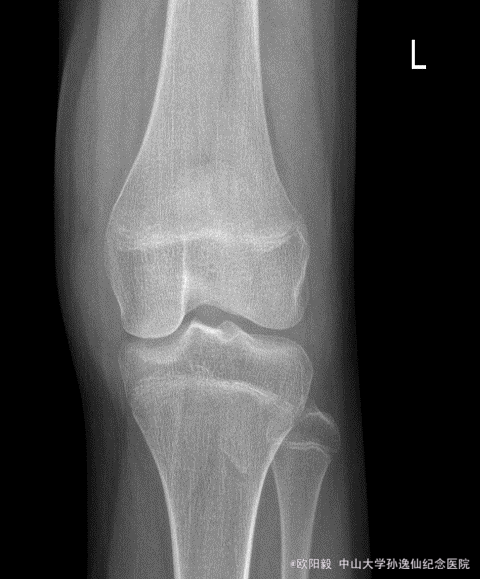

患者女,10岁,因“摔伤致左膝关节反复肿胀1年余”入院。患者1年前摔伤后出现左膝关节肿胀,无明显发热,6个月前曾在外院开放下行左膝滑膜病灶清理术,症状有缓解,但症状仍然反复,余未见明显异常。

查体:左膝关节浮髌征(+),血沉 80,C反应蛋白 15.2,关节液白细胞 41253,余未见明显异常。X线未见明显异常,MRI检查可见髌上囊大量积液。

诊断:左膝关节肿胀查因:感染?拟行左膝关节镜检,病灶清理术。